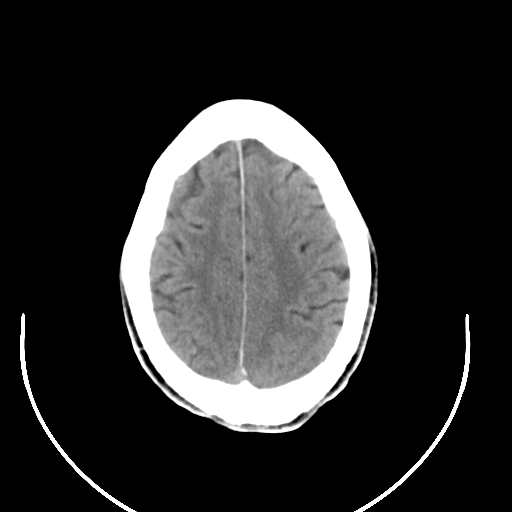

以下是引用拾荒者在2008-7-26 15:36:00的发言:[br]侧脑室内高密度钙化影,未见软组织结构,侧脑室未见增大,考虑良性钙化性改变(钙化型脑膜瘤可能)。

以下是引用宇宙ct在2008-7-26 13:43:00的发言:[br]支持:钙化性脑膜瘤。 不排除脉络膜瘤 [br] [br]